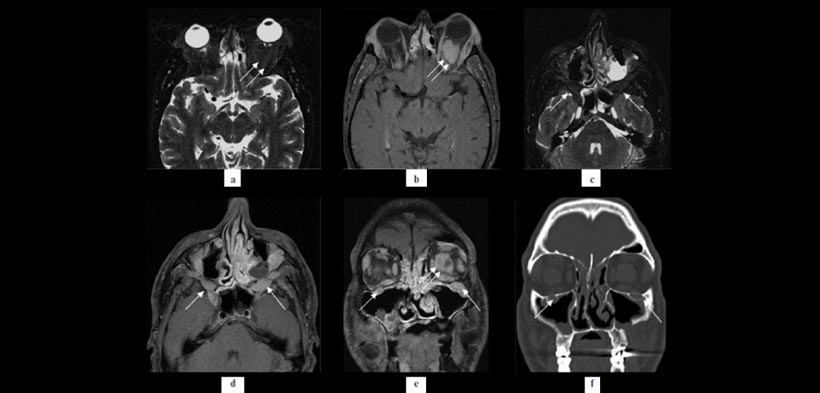

Figura 1. Pseudotumor inflamatoria Bilateral en un paciente masculino de 42 años que presentaba hinchazón periorbital indolora bilateral y proptosis, principalmente en el lado izquierdo: La Resonancia magnética (RM) (a, b) muestra masas bilaterales que ocupan el espacio en ambas órbitas encajonan al nervios ópticos (a, flechas) y que implican fosa pterigopalatino bilateral especialmente en el lado izquierdo (b, flechas). Imágenes de resonancia magnética después de la administración de gadolinio demuestran aumento del contraste leve de las mismas masas (C, D, flechas). No hay extensión a lo largo de los nervios infraorbitario a la fosa pterigopalatino bilateralmente (d, e). El remodelado óseo en el canal infraorbitario se muestra tanto en la RM y también en las imágenes de la tomografía computarizada (E, F, flechas).